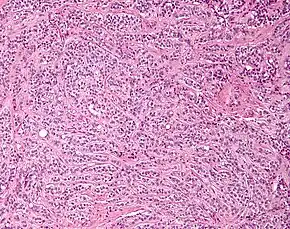

| Micrograph of a Sertoli cell tumour. H&E stain. | |

A Sertoli cell tumour, also Sertoli cell tumor (US spelling), is a sex cord–gonadal stromal tumour of Sertoli cells. They can occur in the testis or ovary. They are very rare and generally peak between the ages of 35 and 50. They are typically well-differentiated and may be misdiagnosed as seminomas as they often appear very similar.[1]

Microscopy and immunohistochemistry are the only way to give a definitive diagnosis, especially when there is a suspected seminoma.[3]